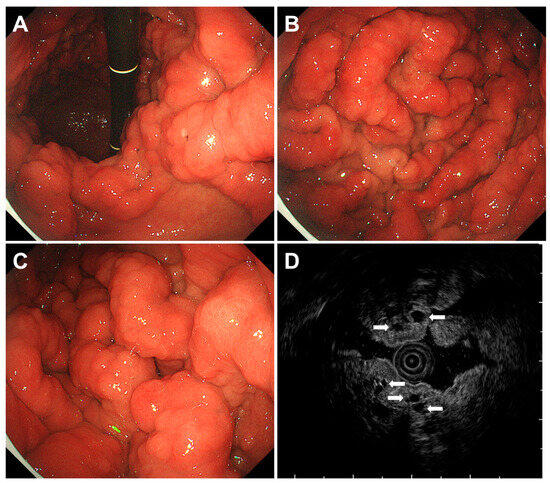

| Cronkhite-Canada syndrome | Not yet elucidated | Gastric polyps ranging from several millimeters to 20 mm in size are observed diffusely as sessile or slightly pedunculated elevations with a dense distribution. Edema with inflammation is present in the intervening mucosa between the polyps. |

| Juvenile polyposis syndrome | Mutations in the SMAD4 or BMPR1A gene | Papillary or tongue-like polyps, multiple and reddish in color of varying sizes with swollen or edematous features. |

| Multiple submucosal heterotopic glands | Chronic inflammation, such as infection of Helicobacter pylori | Polypoid lesions with cystic areas beneath the gastric mucosa visualized during an endoscopic ultrasound examination. |